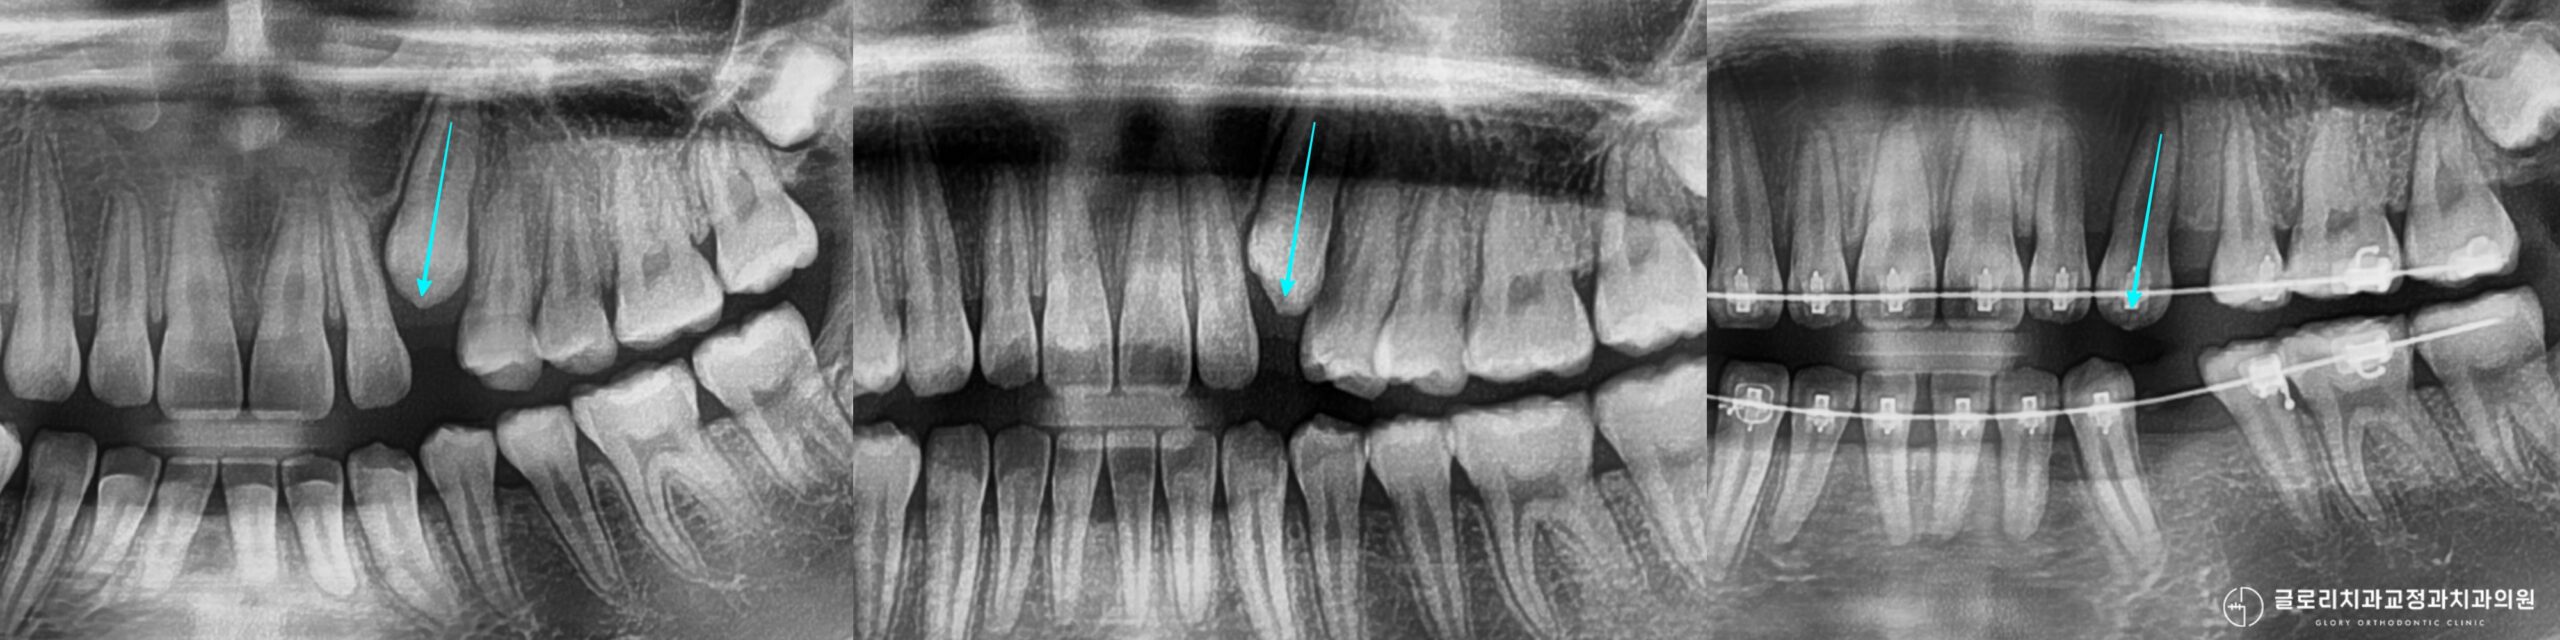

위 사진에서 확인할 수 있듯이 파노라마 엑스레이를 통해 치아 전체의 맹출 상태를 파악할 수 있습니다.

그러나 매복된 송곳니의 정확한 위치와 주변 치아 뿌리와의 관계를 확인하려면 CT 촬영이 필수적으로 병행되어야 합니다.

사진에서 보이는 것처럼 발치 후 생긴 공간은 돌출된 앞니를 후방 이동시키는 데 사용되며 동시에 매복된 송곳니가 나올 자리를 마련하는 역할도 하게 됩니다.

치료기간 : 23.07.25 ~ 25.10.21